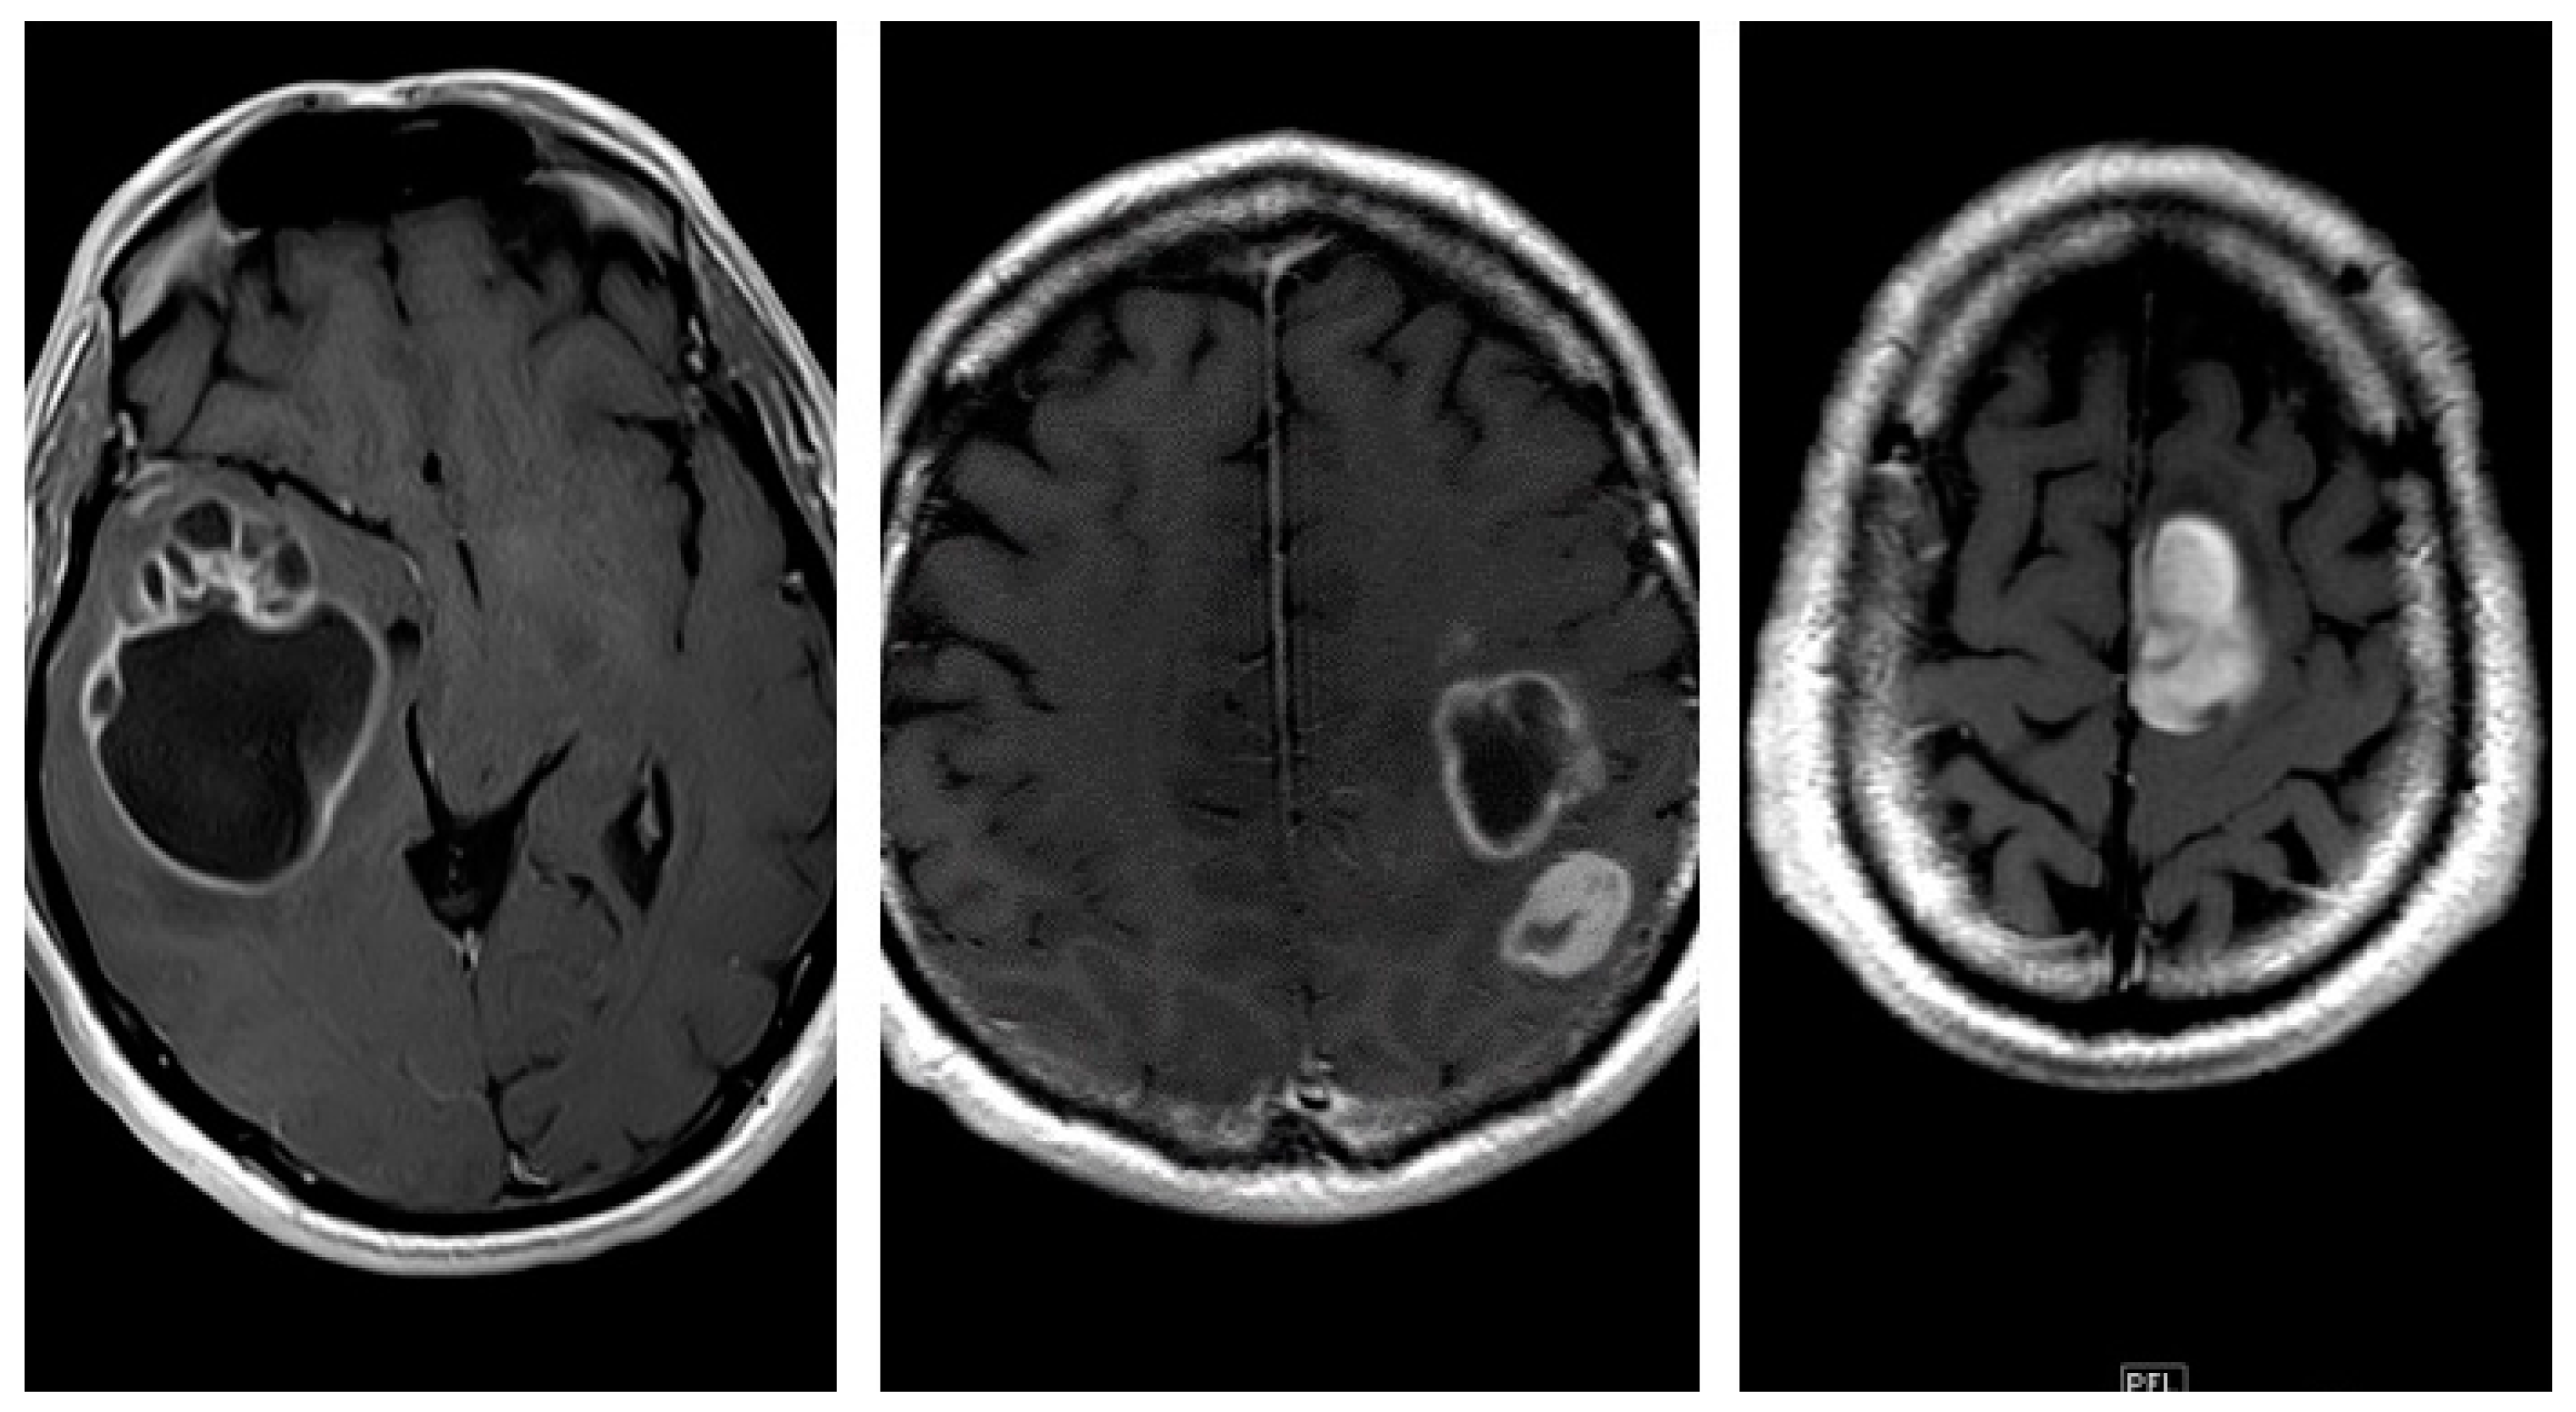

CE-PTV was evaluated on 2D axial Contrast Enhanced T1 weighted (CE-T1w) images (slice thickness: 5 mm.; slice spacing: 5,5-6 mm.), by contouring manually enhanced tumor areas on every single axial slice, excluding necrosis; the same analysis was subsequently performed with semi-automatic method by using the apposite tool of the AW server 3.2 [Figure 1 and Figure 2].

Figure 1. CE-PTV manual evaluation.

Figure 8. thin, enhancing wall thickness < 3 mm (left).; thin-nodular, when the enhancing wall showed focal thickenings > 3 mm (center).; nodular, when solid appearance was predominant and intra-tumoral necrosis absent or less than 1,5 cm³ (right).